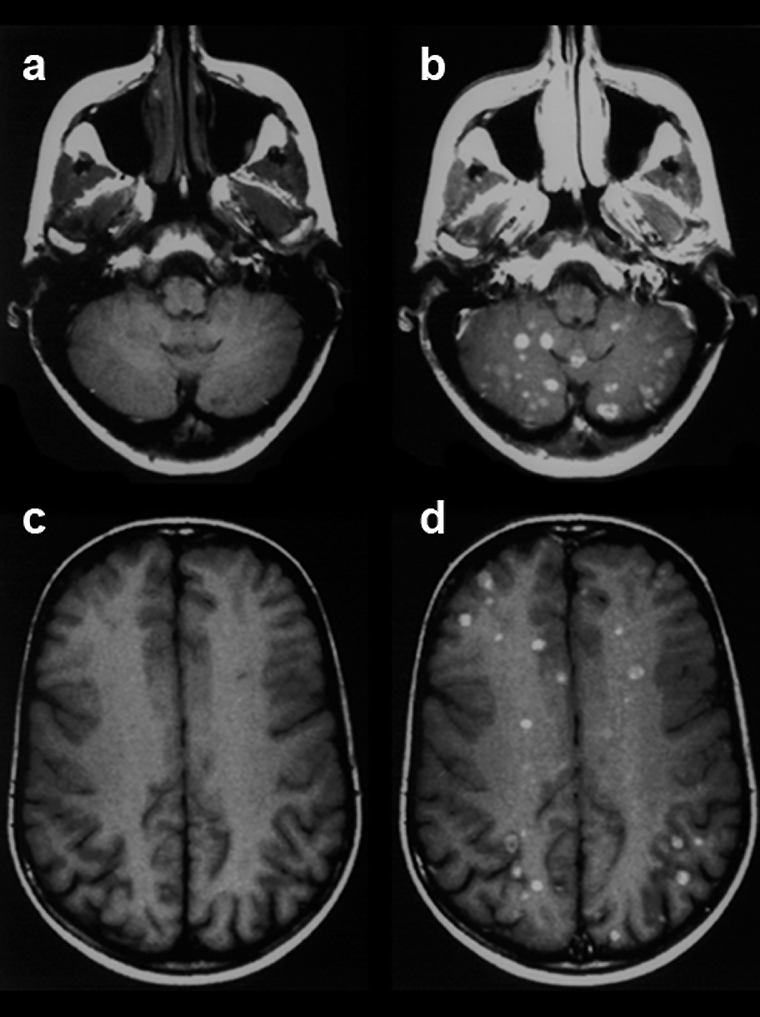

Figura 13-03:

This figure gives an example of a clinical case where finally the application of such a po­si­ti­ve contrast agent helped the diagnostic process and showed the extent of the disease: Patient with breast cancer and recent neurological symptoms. T1-weighted images. The plain MR ima­ges (pre­con­trast: a and c) do not reliably reveal brain lesions. However, the contrast-enhanced MR images (postcontrast: b and d) show a large number of metastases.